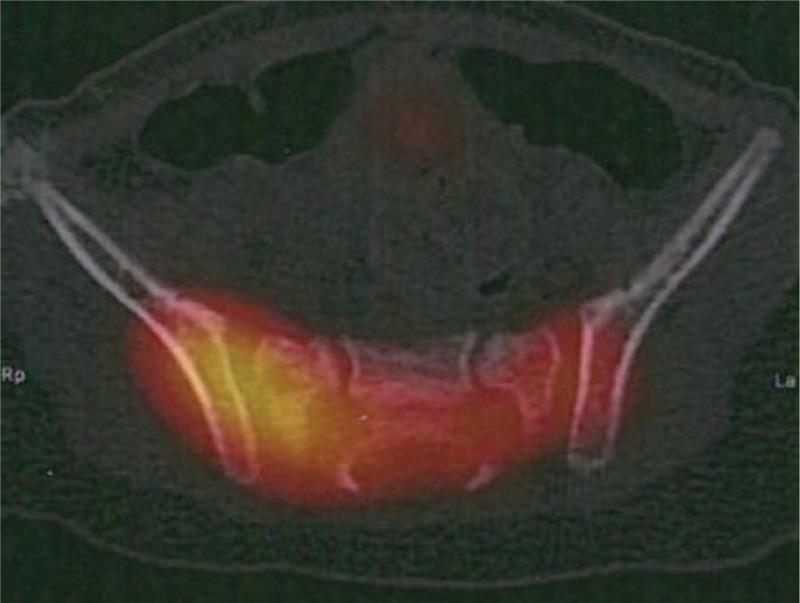

Pyogenic sacroiliitis is exceptional in very young children. Diagnosis is difficult because clinical examination is misleading. FABER test is rarely helpful in very young children. Inflammatory syndrome is frequent. Bone scintigraphy and MRI are very sensitive for the diagnosis. Joint fluid aspiration and blood cultures are useful to identify the pathogen. Appropriate antibiotic therapy provides rapid regression of symptoms and healing. We report the case of pyogenic sacroiliitis in a 13-month-old child.Clinical, biological, and imaging data of this case were reviewed and reported retrospectively.A 13-month-old girl consulted for decreased weight bearing without fever or trauma. Clinical examination was not helpful. There was an inflammatory syndrome. Bone scintigraphy found a sacroiliitis, confirmed on MRI. Aspiration of the sacroiliac joint was performed. Empiric intravenous biantibiotic therapy was started. Patient rapidly recovered full weight bearing. On the 5th day, clinical examination and biological analysis returned to normal. Intravenous antibiotic therapy was switched for oral. One month later, clinical examination and biological analysis were normal and antibiotic therapy was stopped.Hematogenous osteoarticular infections are common in children but pyogenic sacroiliitis is rare and mainly affects older children. Diagnosis can be difficult because clinical examination is poor. Moreover, limping and decreased weight bearing are very common reasons for consultation. This may delay the diagnosis or refer misdiagnosis. Bone scintigraphy is useful to locate a bone or joint disease responsible for limping. In this observation, bone scintigraphy located the infection at the sacroiliac joint. Given the young age, MRI was performed to confirm the diagnosis. Despite the very young age of the patient, symptoms rapidly disappeared with appropriate antibiotic therapy.We report the case of pyogenic sacroiliitis in a 13-month-old child. It reminds the risk of misdiagnosing pyogenic sacroiliitis in children because it is exceptional and clinical examination is rarely helpful. It also highlights the usefulness of bone scintigraphy and MRI in osteoarticular infections in children.